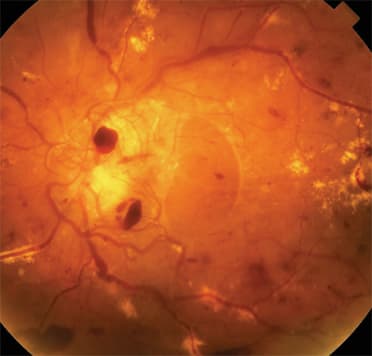

Top: Mild non-proliferative diabetic retinopathy (NPDR) or background diabetic retinopathy with microaneurysms and retinal hemorrhage Bottom: Moderate non-proliferative diabetic retinopathy with retinal hemorrhages, exudates, and diabetic macular edema (DME)

Top: Proliferative diabetic retinopathy (PDR) with extensive retinal hemorrhages and neovascularization of the optic nervehead Bottom: Severe proliferative diabetic retinopathy (PDR) with hemorrhages, exudates, neovascularization, fibrosis, and traction retinal detachment |

NPDR is caused by the development of microaneurysms in capillary walls. Its clinical manifestations include hemorrhages, microaneurysms, venous beading, hard exudates (often coalescing in the macula), and diabetic retinal edema (DRE). (See images above.)

Proliferative diabetic retinopathy (PDR) is the most severe form of diabetic retinopathy, resulting from persistent and profound retinal ischemia, leading to neovascularization of the retina and the optic nervehead, retinal and vitreous hemorrhage, and retinal scarring and fibrosis ending in traction retinal detachment. (See images above.)